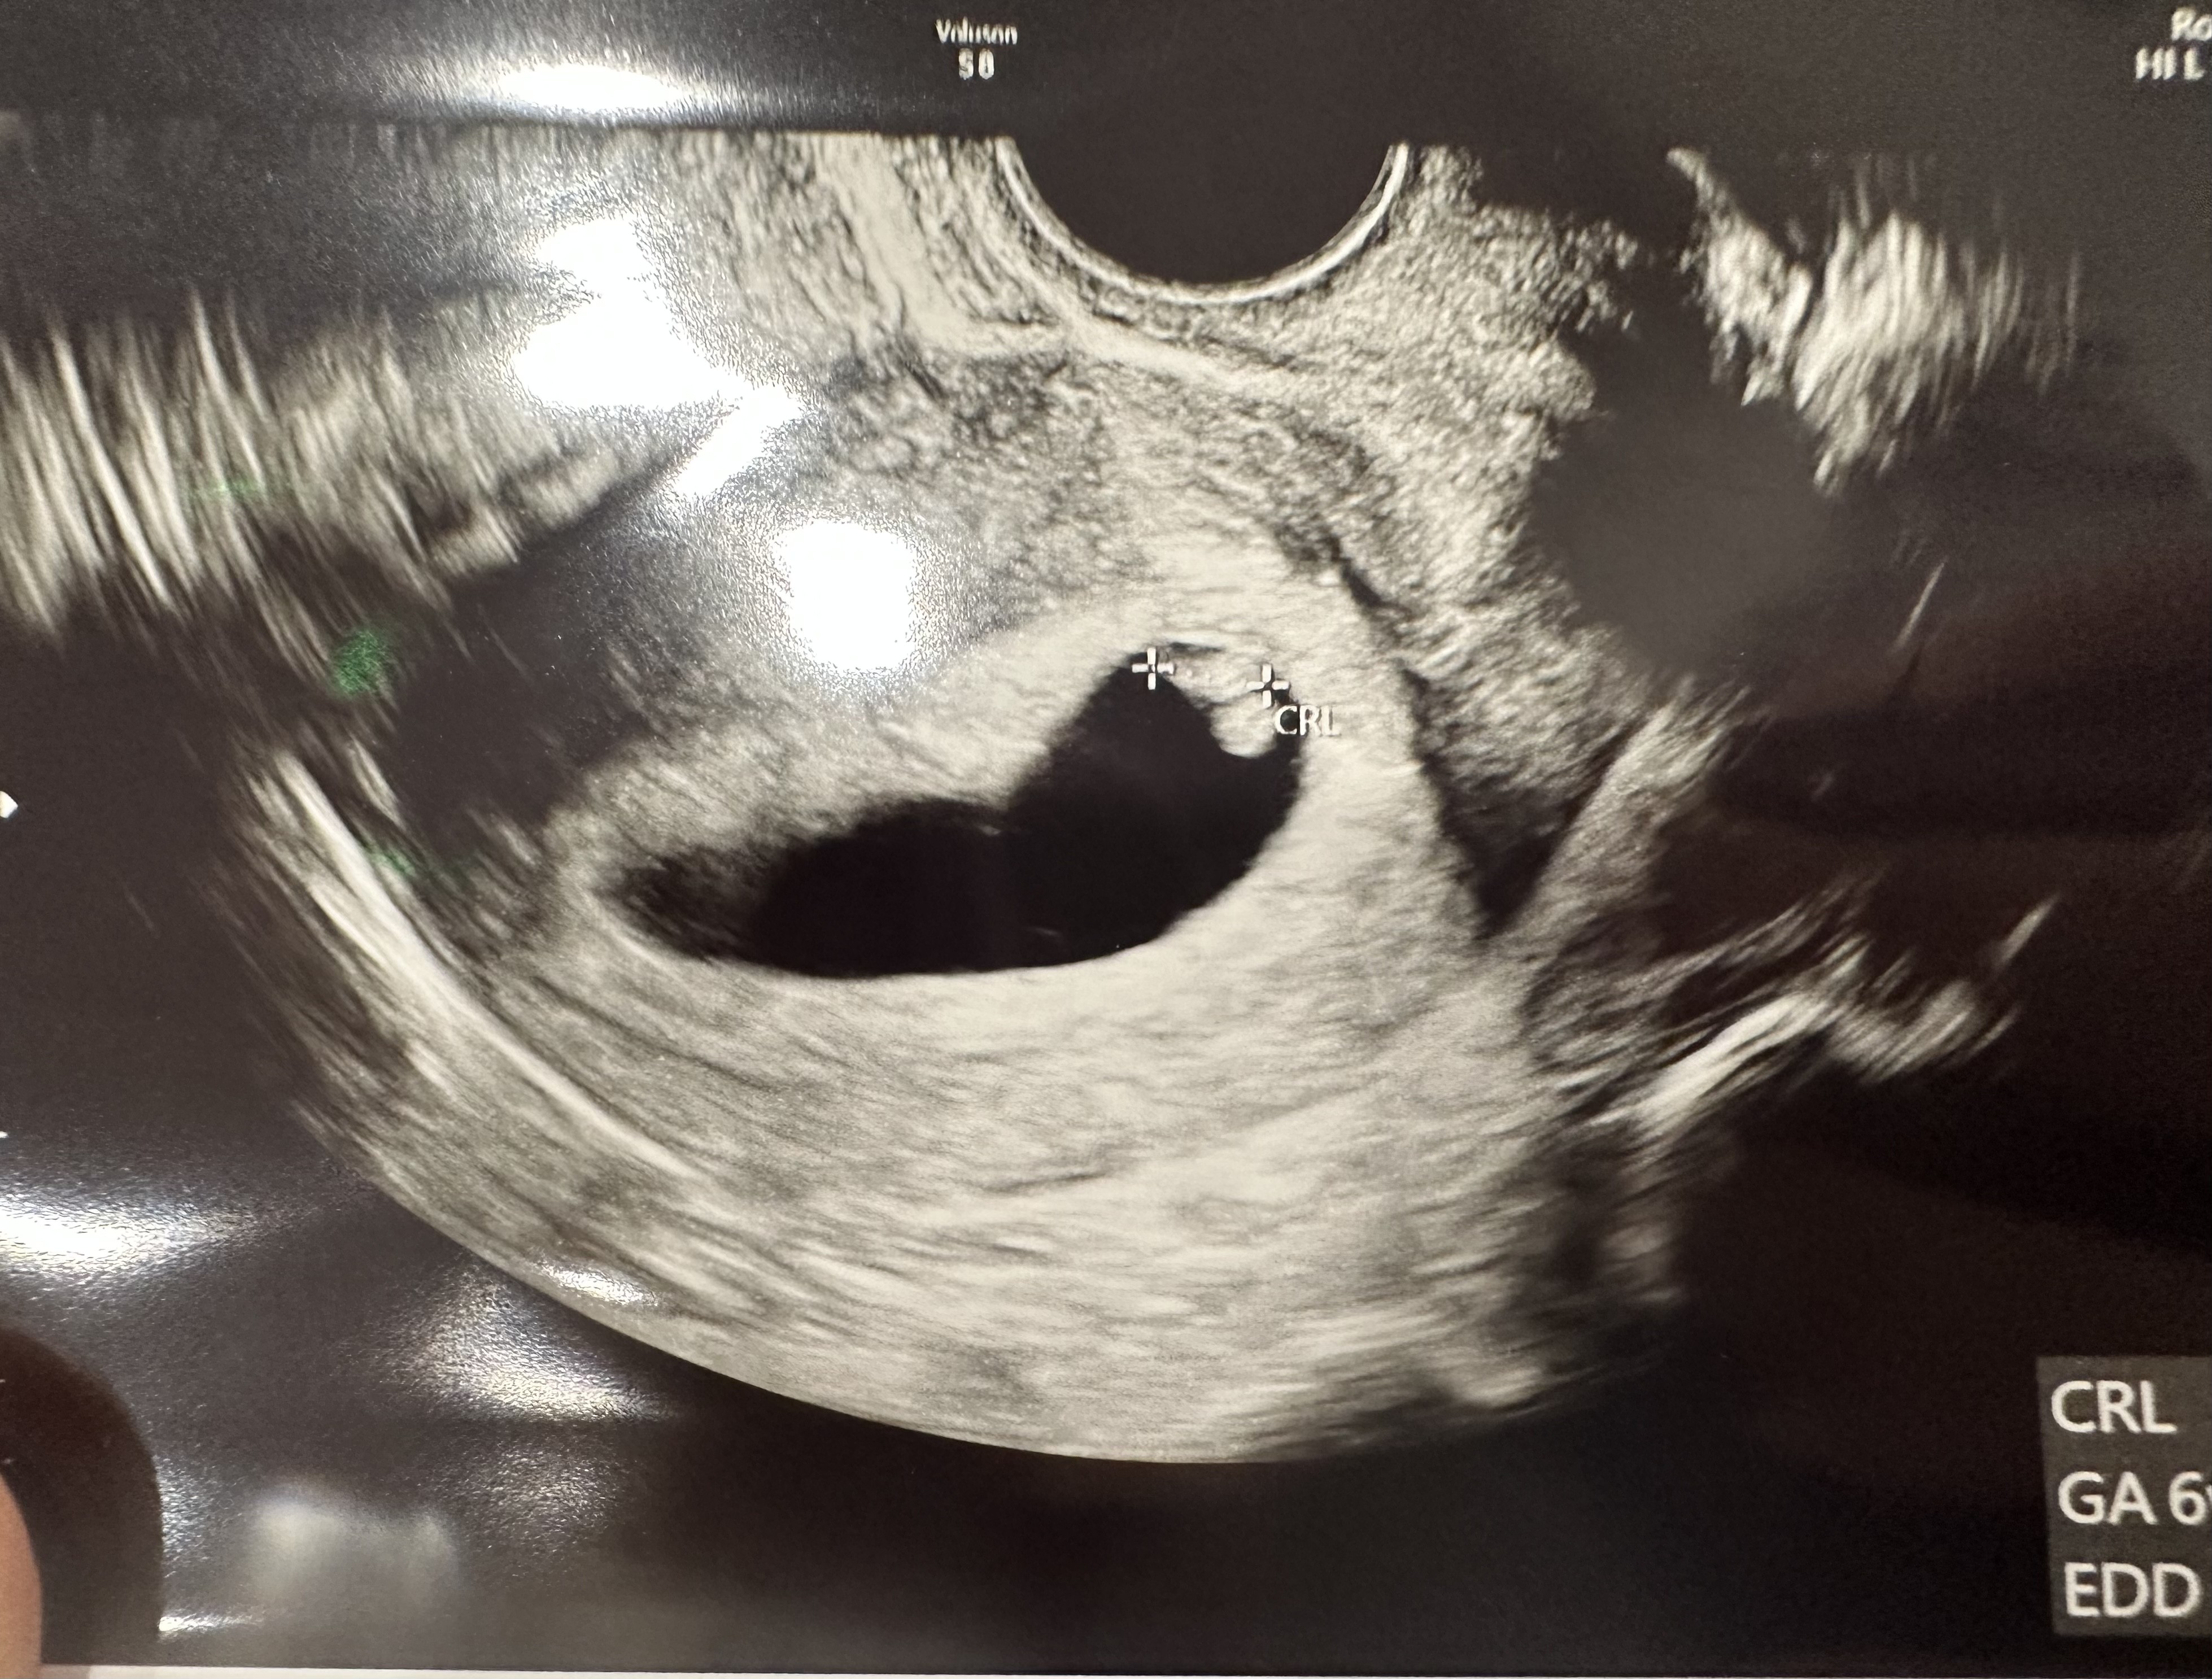

Gratuluję, cudowne wieściDziewczyny, jestem! Dopiero wróciłam z kliniki. Dziękuję za wszystkie Wasze dobre myśli, a czuje, ze poszło ich do wszechświata mnóstwo, bo oto mamy 6,8mm człowieka i bijące serce!plamieniami mam sie nie przejmować bo nie są mocne (dobre sobie, sami niech sie nie przejmują). Jesteście absolutnie kochane, bez Was bym oszalała

Zobacz załącznik 1511058